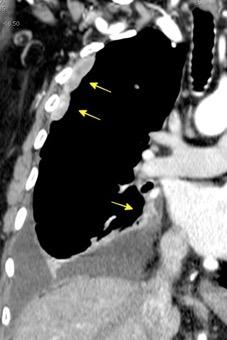

100. TUMOR FANTASMA

En relación con trasudados tabicados. Insuficiencia cardiaca

Derrame pleural “encapsulado”

“Tumor fantasma”

Asociado a fallo cardiaco. ( “Pleuritis adhesiva”). Buch KP. Chest. 2000